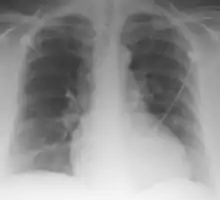

| Palla Sign and Westermark Sign | |

Palla's sign is a clinical sign in which an enlarged right descending pulmonary artery is seen on the chest x-ray in patients with pulmonary embolism. It is of low sensitivity, and its specificity is not known. It exhibits as a "sausage" appearance on X-ray. [1] It is named after italian radiologist Antonio Palla. In 1983, he published his observations that close to 25% of patients with pulmonary embolism had a chest x-ray sign of enlarged right descending pulmonary artery.[2][3]